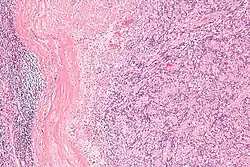

| Micrograph of an intranodal palisaded myofibroblastoma. H&E stain. | |

IPMs are diagnosed by examination of the tissue by a pathologist. They have a rim of peripheral lymphoid tissue (remnant of a lymph node) and consist of spindle cells with nuclear palisading. Red blood cell extravasation is common and blood vessels surrounded by collagen with (fine) peripheral spokes (amianthoid fibers) are usually seen.[2]

Immunostains for smooth muscle actin and cyclin D1 are characteristically positive. The main histologic differential diagnosis is schwannoma.

Low mag.